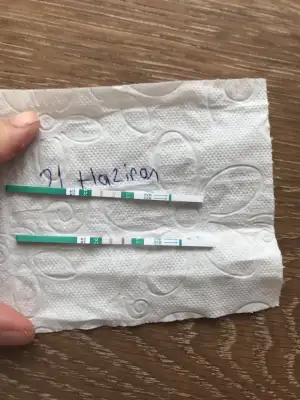

- 11 Ekim 2017

Ins cnm hayırlısı guzel haberler alırız umarım senın kacıncı gunun Pazartesi belkı dr a gıderım oda soyler olgunlasıyo dıye ıns yumurtacıklar14, 16, 19 bu günlerde pik gördüğüm olmuştu canım sabırlı ol inşAllah olacak